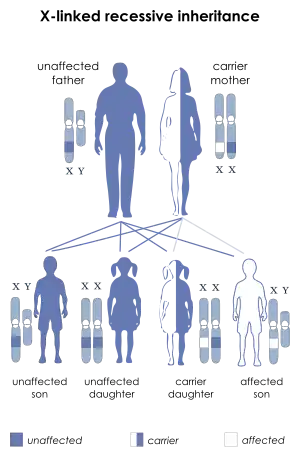

The disorder is X-linked recessive.[2] About two thirds of cases are inherited from a person's mother, while one third of cases are due to a new mutation.[2] It is caused by a mutation in the gene for the protein dystrophin.[2] Dystrophin is important to maintain the muscle fiber's cell membrane.[2] Genetic testing can often make the diagnosis at birth.[2] Those affected also have a high level of creatine kinase in their blood.[2]

DMD is inherited in an X-linked recessive pattern. Females typically are carriers of the genetic trait while males are affected. A female carrier will be unaware she carries a mutation until she has an affected son. The son of a carrier mother has a 50% chance of inheriting the defective gene from his mother. The daughter of a carrier mother has a 50% chance of being a carrier and a 50% chance of having two normal copies of the gene. In all cases, an unaffected father either passes a normal Y to his son or a normal X to his daughter. Female carriers of an X-linked recessive condition, such as DMD, can show symptoms depending on their pattern of X-inactivation. DMD has an incidence of one in 3,600 male infants.[10] Mutations within the dystrophin gene can either be inherited or occur spontaneously during germline transmission.

DMD is extremely rare in females (about 1 in 50,000,000 female births).[4] It can occur in females with an affected father and a carrier mother, in those who are missing an X chromosome, or those who have an inactivated X chromosome (the most common of the rare reasons).[16] The daughter of a carrier mother and an affected father will be affected or a carrier with equal probability, as she will always inherit the affected X-chromosome from her father and has a 50% chance of also inheriting the affected X-chromosome from her mother.[17]